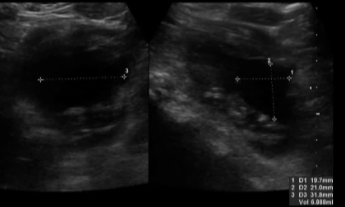

几个月后发现肿块复发,超声检查证实为囊性复发。在硬化前进行抽吸和第二次细胞学检查以确认良性

10ml 无水乙醇硬化治疗